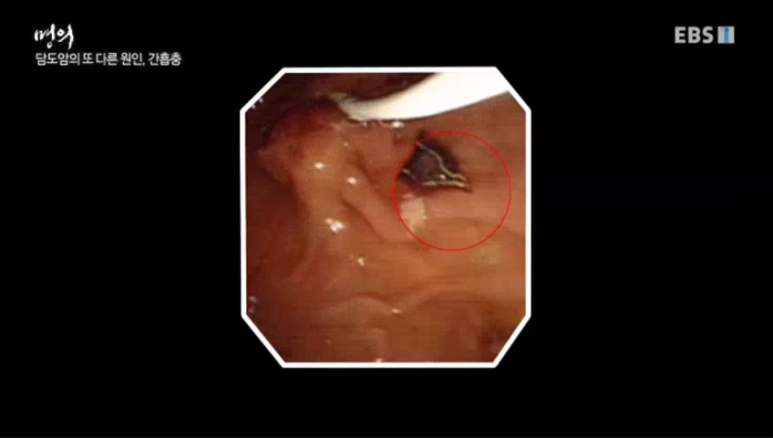

사진에서 보이는 것이 간흡충이다 간흡충은 담도에 오래 기생하지만 길게는 2030년까지 기생한다.